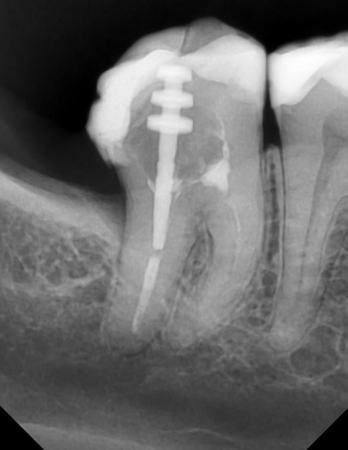

В овалах штифтовые конструкции. В прямоугольнике видна горизонтальная исчерченность — это помехи от металла штифта.

Если мы видим такие помехи, то делаем единичный прицельный снимок, где отражение уже не мешает:

Тот же зуб из примера выше на прицельном снимке